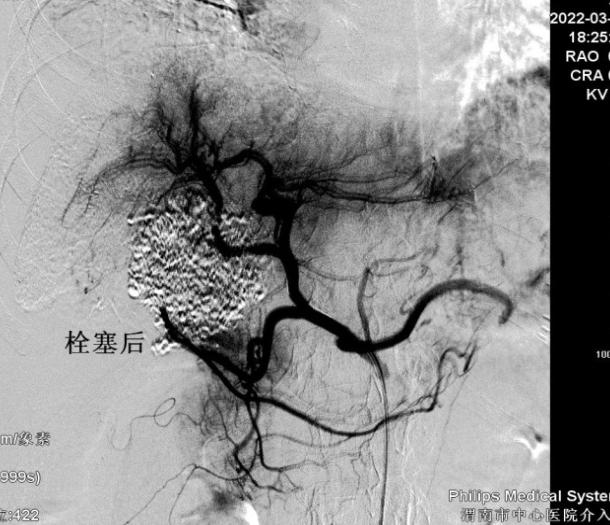

患者女性,57岁,3月12日,突发腹部疼痛就诊于当地医院,CT示肝肿瘤破裂出血,随即转入市中心医院急诊科,分诊后入住普外科二病区。急查实验室检查示:血红蛋白71g/L,血压85/60mmHg左右,正值周日,值班人员电话紧急请介入科会诊,经分析,患者随时有失血性休克风险,当即立断启动疫情状态下的急危重症患者介入诊疗绿色通道。应急值班人员第一时间到位,行肝动脉造影明确了出血动脉(部位),现场评估并制定了手术方案,对肿瘤出血进行了封堵及TACE,术后给予止血、保肝、输血、抗感染等对症处理,病情稳步好转。复查CT肝内碘油沉积良好(提示介入治疗疗效佳),目前已安全出院。

该患者诊断及时,采取介入治疗迅速有效,避免了外科开腹手术,减少了创伤。